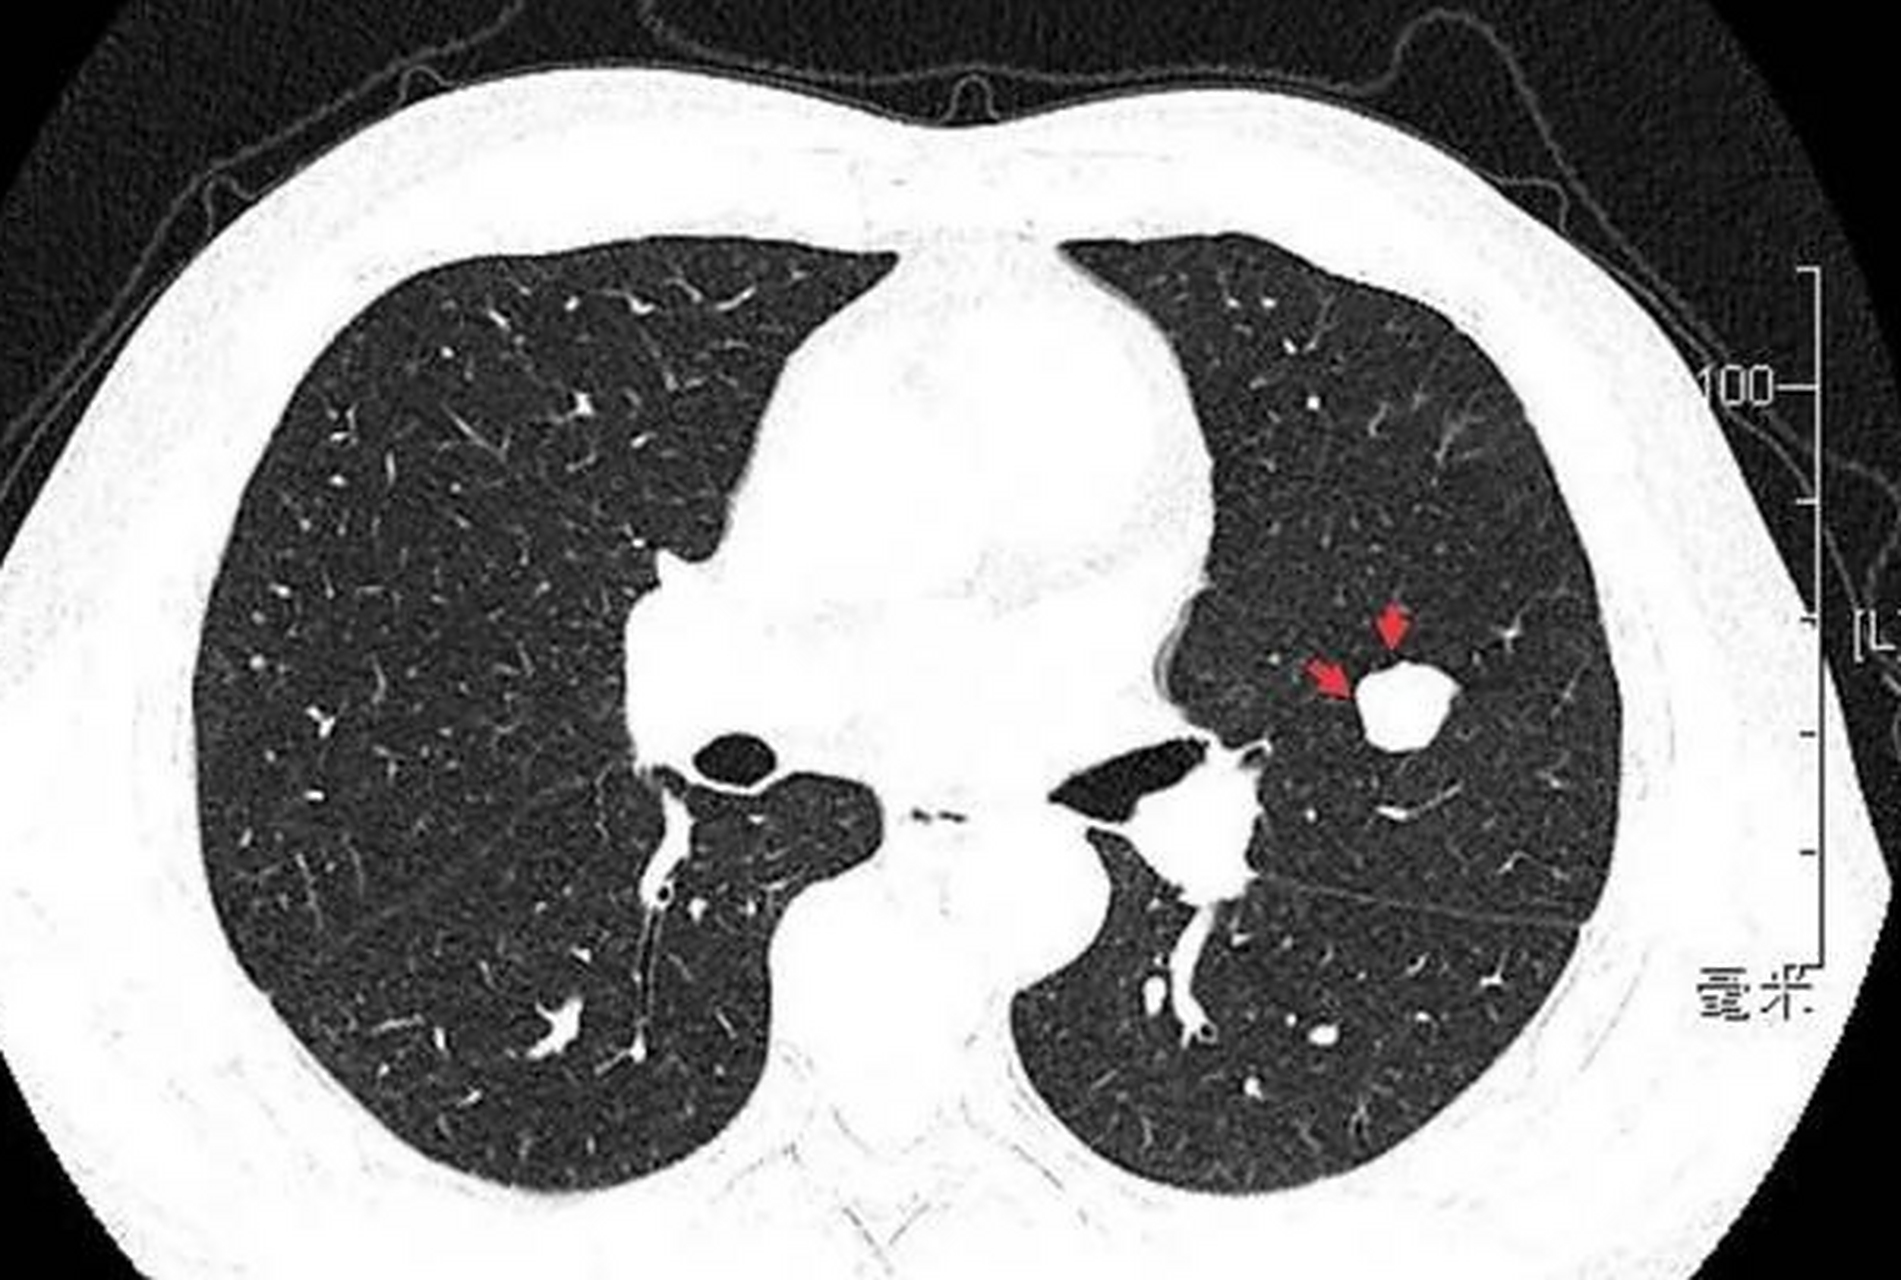

肺泡微石症:呼吸系统的罕见石化疾病 在我们的生活中,石化常常被与